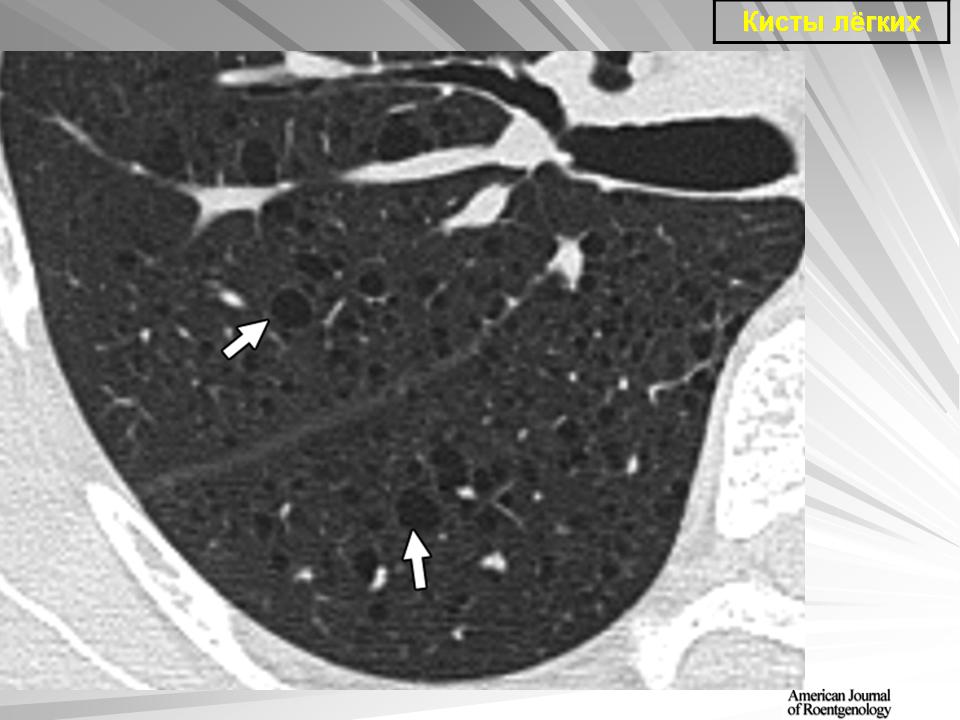

Легочные кисты.

Приложения:

1.ki_.slayd107.jpg2.ki_.slayd108.jpg3.ki_.slayd109.jpg